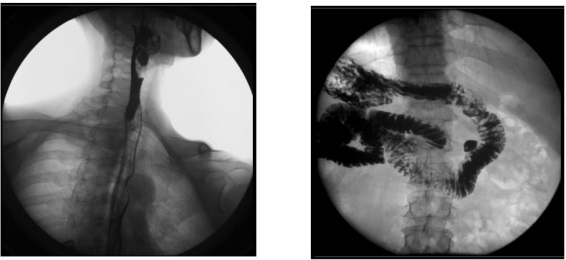

2、數字化胃腸功能:適用于胃腸道造影檢查,如食管造影、上消化道造影、全消化道造影等。

1) 消化內科:可檢查直腸炎、結腸炎等;

臨床表現為腹痛、便秘等,癥狀為便血、黑便等。

2) 肛腸科:可應用氣鋇雙重造影和排便造影(DFG)功能,可檢查大腸的細小病變,如小息肉、早期腫瘤、潰瘍等效果良好;可檢查肛管炎、恥骨直腸肌綜合癥、骶骨部畸胎瘤、直腸前突、直腸內套疊、肛門直腸損傷和異物等檢查。

3、其他造影:適用于各種普通及特殊造影,如口服膽囊造影、靜脈膽道造影、T 管造影、逆行胰膽管造影(ERCP)、靜脈腎盂造影(IVP)、子宮輸卵管造影等。

1) 婦科:可檢查輸卵管堵塞、輸卵管粘連、輸卵管積水等慢性輸卵管疾病導致的不孕,可明確顯示輸卵管堵塞的部位、程度及性質,還可辨認子宮內膜情況,輸卵管和盆腔的結核病變情況;

2) 肝膽外科:膽管手術后,切開膽總管植入 T 管引流,起支撐作用,防止術后膽總管狹窄,術后應用胃腸機進行膽管造影(T 管造影),檢查膽道內有無殘留結石及異物,是否通暢無阻, 對手術進行評估;